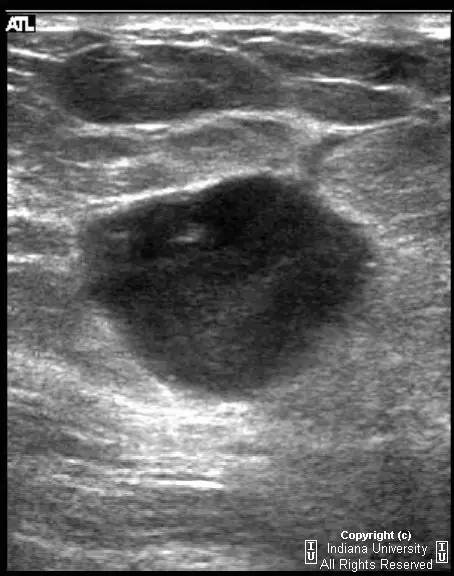

乳腺钼靶左乳腺内上象限见3.1cm卵圆形等密度肿块,部分界限清晰。超声见一2.5 x 2.1 x 1.9 cm混合回声肿块,宽大于高,边界清晰,后部回声增强。

浸润性导管癌

Invasive ductalcarcinoma